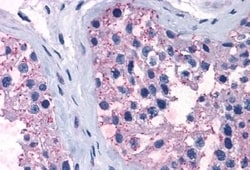

Invitrogen™ TAS1R1 Polyclonal Antibody

| Immunohistochemistry (Paraffin) | |

| Synthetic 16 amino acid peptide from 3rd cytoplasmic domain of human TAS1R1. | |

| Human, Canine, Bovine, Pig, Horse | |